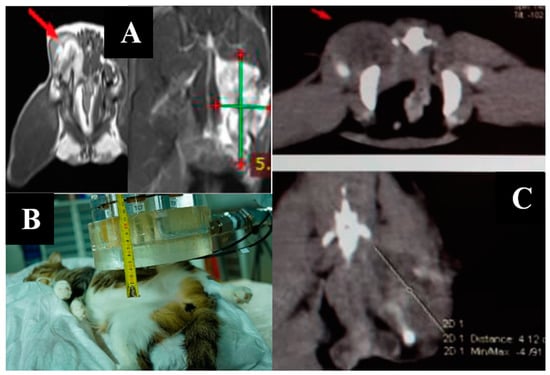

3.5. Case 5

3.6. Case 6

3.7. Case 7

3.8. Case 8